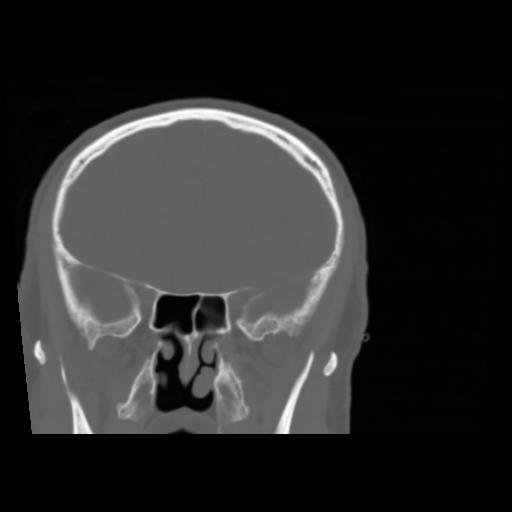

5 CEREBRO,,Coronal,3.000,CEREBRO,Coronal,